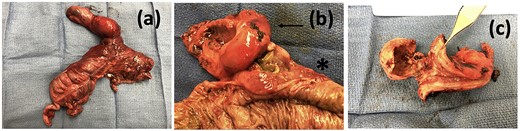

Case presentation #2: A 39-year-old male initially presented with acute cholecystitis (AC) with a markedly thickened wall with abscess formation, not amenable for drainage, treated with antibiotics with improvement, but later experienced recurrent biliary colic symptoms. Repeat computed tomography (CT) imaging (Fig. 4) 2 months later showed a peripherally hyperdense septated collection within the porta hepatis with surrounding fluid signal attenuation; likely representing an abscess seen around the gallbladder possibly secondary to gallbladder perforation due to neoplastic versus inflammatory pathology. Ultrasound showed chronic cholecystitis with cholelithiasis. The patient later underwent elective laparoscopic cholecystectomy. Intraoperatively, extensive adhesions from the liver to the gallbladder and the colon to the gallbladder were noted. The fundus of the gallbladder was densely adherent to the hepatic flexure with no dissection plane. The hepatic flexure felt firm, raising concern of a possible tumor or fistula. The decision was made to remove the right colon en-bloc with the gallbladder. The gallbladder was dissected free in the usual manner and a critical view was obtained. Once the gallbladder was freed, we proceeded with a laparoscopic right hemicolectomy with ileocolonic anastomosis. The specimen was evaluated on the back table; no tumor was seen, but there was what appeared to be an abscess cavity adherent between the gallbladder and colon filled with green stool-colored liquid. The patient tolerated the procedure well and was progressively advanced to regular diet postoperatively and discharged on postoperative Day 3. His final pathology of the operative specimen (Fig. 5) came back as acute on chronic cholecystitis with a micro-fistula between the gallbladder and the adjacent colon.

Operative specimen showing the gallbladder and colon resected in bloc (a) En-bloc specimen (b) Gallbladder (arrow) tightly adherent to colon (start) and (c) macroscopic appearance of the cholecystocolonic fistula.